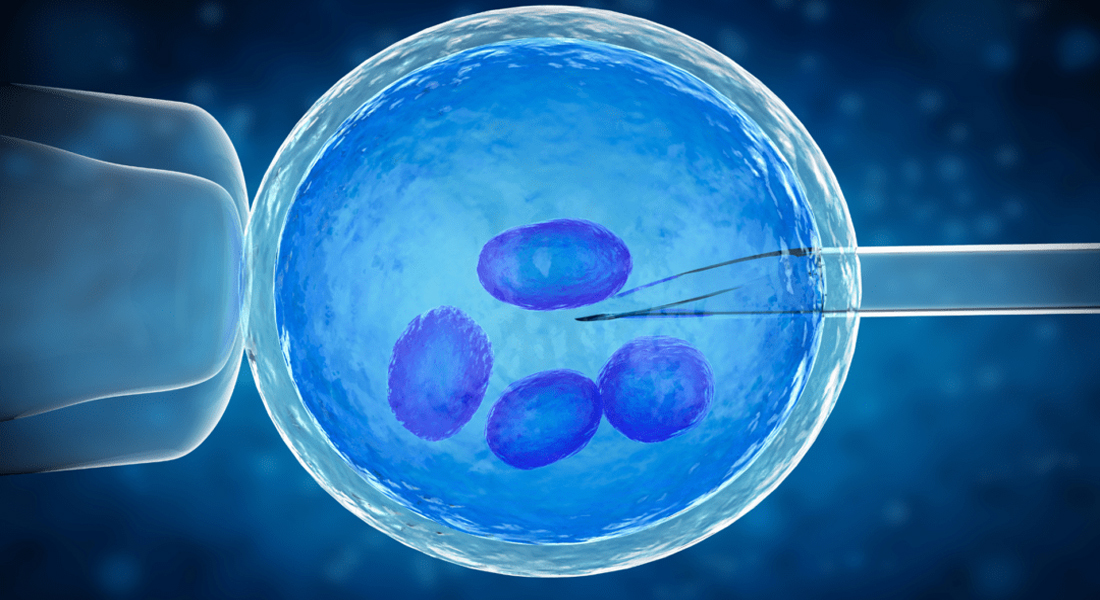

Advanced Technology

Cutting-edge treatments for higher success.